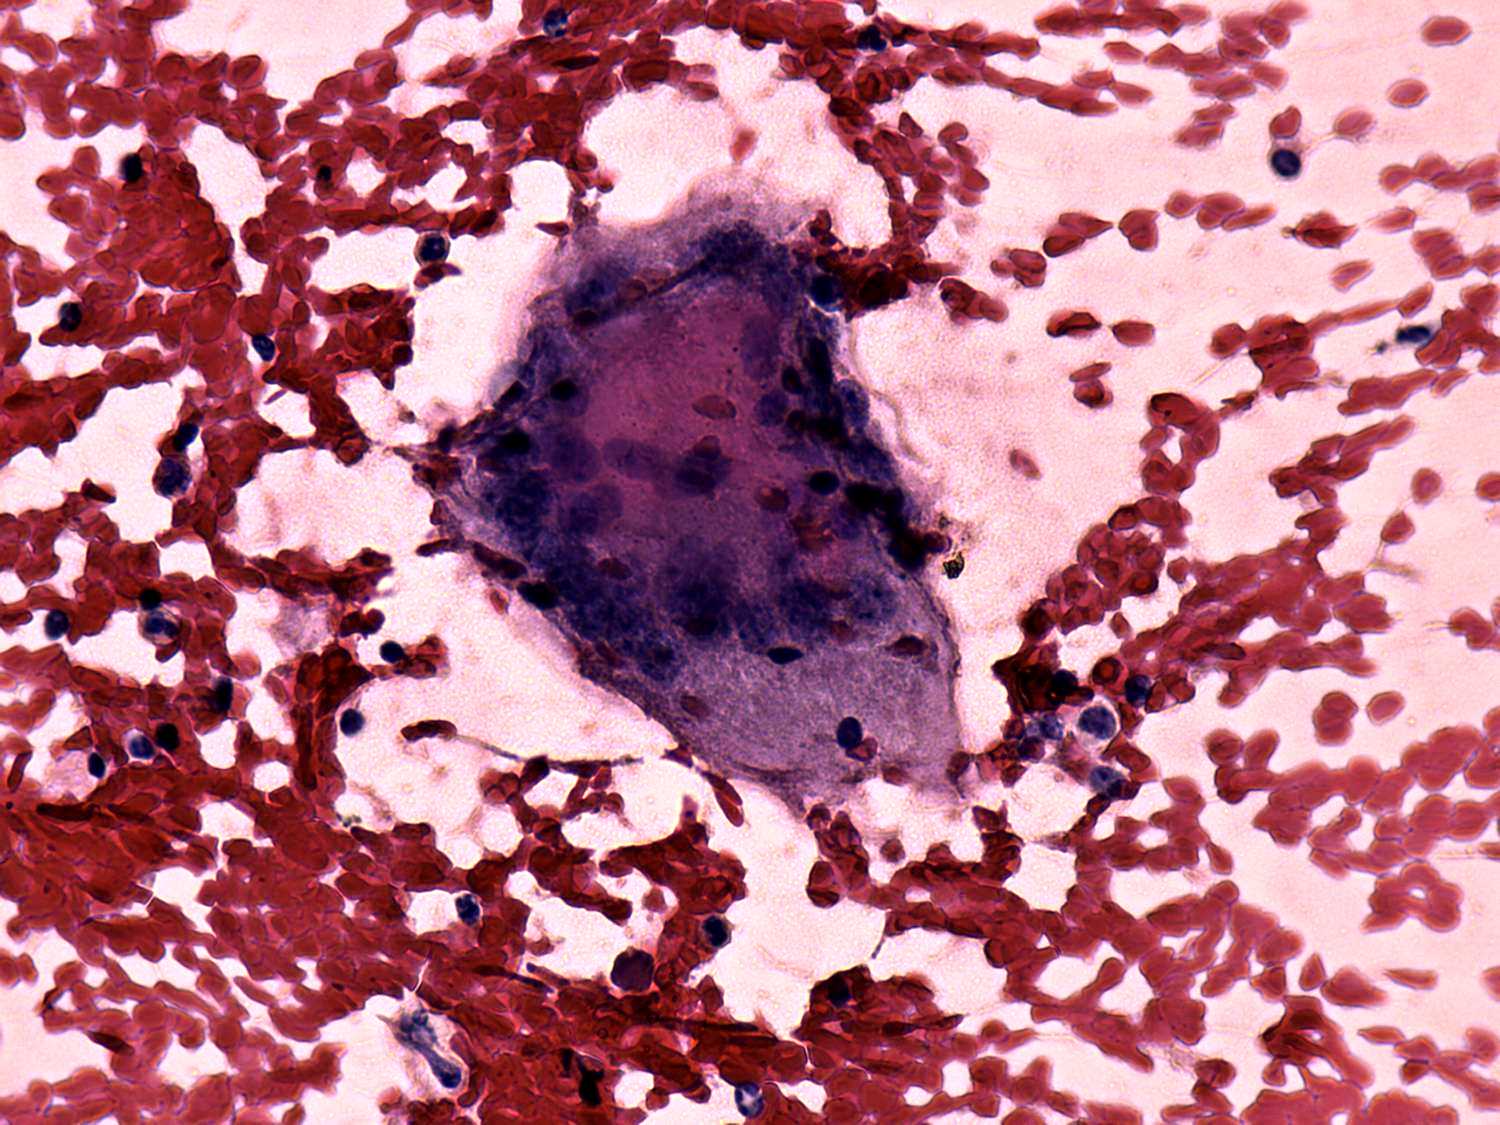

De Quervain's thyroiditis - Figure 3. Cytological presentation.

In the event of a de Quervain's thyroiditis multinucleated giant cells are in fact part of the granulation tissue. This is the most important cytological sign of de Quervain's thyroiditis. Naturally, in a cytological sample we cannot analyze an intact tissue. Therefore we must keep in mind that the finding of multinucleated giant cells on a smear itself is not enough to give the diagnosis of de Quervain's thyroiditis because benign hyperplastic nodules, papillary carcinoma, Hashimoto's thyroiditis and granulation around surgical thread may also present this cell type.

On the other hand, a multinucleated giant cell composed of elongated epitheloid cells is an almost pathognomic finding. The images in the first row demonstrate multinucleated cells composed of follicular cell while the images in the second row present multinucleated giant cells composed of epitheloid cells. The multinucleated cells in the third row contain both follicular cells and epitheloid cells.